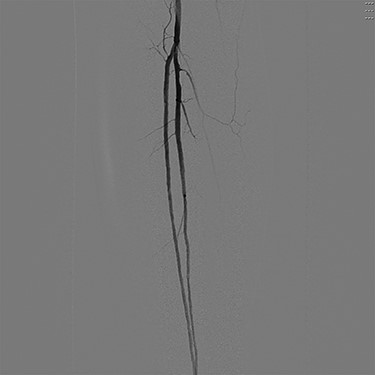

Angiography (Figs 1 and 2) demonstrated bilateral hypoplasia of the posterior tibial arteries (PTA), with the anterior tibial artery supplying most of the blood to the forefoot. The peroneal arteries were also noted to provide large collateral branches posteriorly and were the primary arterial supply to the heel. Additionally, the medial plantar artery (MPA) arising from the PTA was nearly absent and the plantar arch was incomplete bilaterally.

Digital subtraction angiography of the left popliteal artery and its tibial branches, demonstrating a hypoplastic posterior tibial artery.